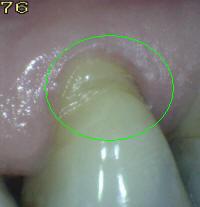

Código 1:

Hay una zona

claramente delimitada

en la

superficie de la raíz

o en la unión

cemento-esmalte

(UCE)

que es de color (claro,

oscuro, marrón y negro),

pero no hay

cavidad

presente,

(pérdida del

contorno anatómico

menor a

0,5

mm)

detectable con sonda periodontal. |